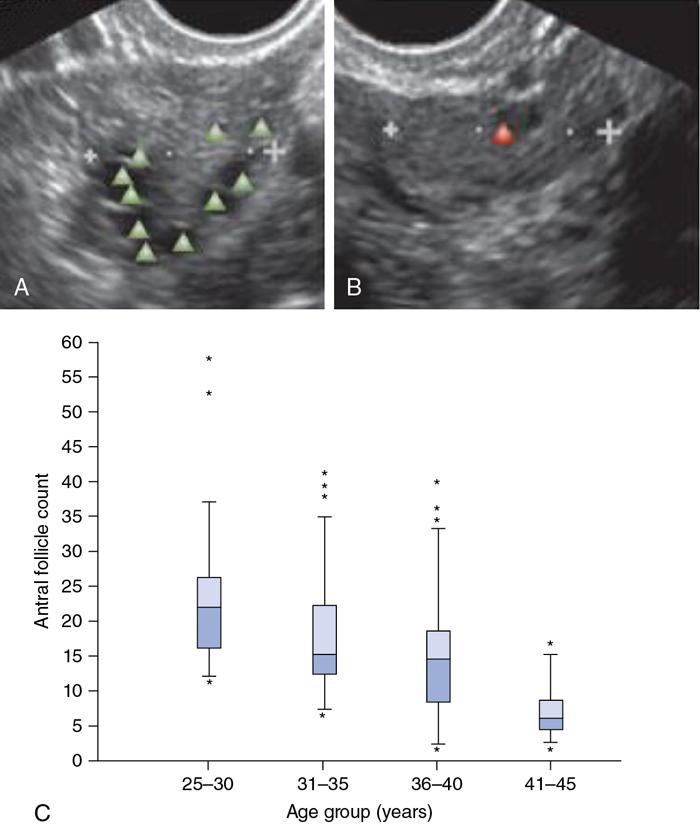

• Ovarian antral follicle count (AFC) is a noninvasive, easily performed technique that can be used as a surrogate marker for the reserve of each ovary separately (Fig. 11.20.1.6).

• AFC is preferentially done in the early follicular phase of the menstrual cycle to minimize the effect of intracycle variation (of follicular diameters) and reduces the likelihood of the presence of an ovarian cyst or a corpus luteum, which might mask some antral follicles

• Size of antral follicle – 2 to 10 mm

• Total AFC – Total number of follicles seen in both ovaries – used in assisted reproduction centres.

• Total AFC – 4 to 20 – varies every month

Image

Fig. 11.20.1.6 (A) Marks the antral follicles in transverse section. (B) Measurement of ovary in longitudinal scan. (C) Relationship of AFC with respect to age group.

Follicular number per ovary (FNPO) – useful in gynaecological clinical practice.